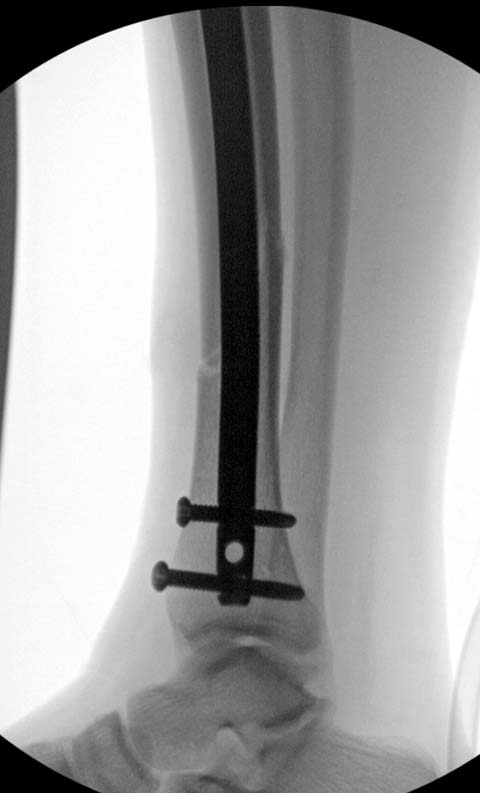

Здесь несколько снимков изолированного перелома большеберцовой с

интактной малоберцовой.  Weber clamp, блокирующие спицы и риминг в

центре канала отрепонировал перелом....